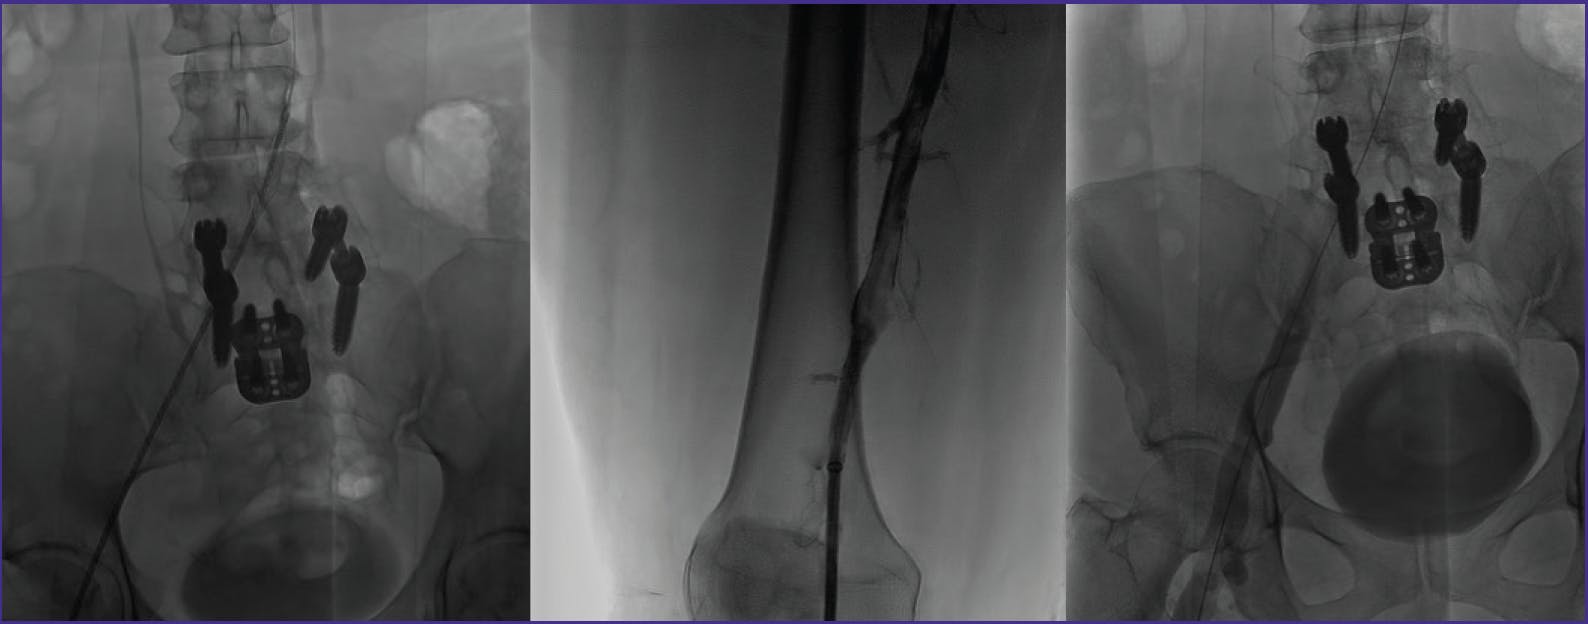

The .035 guidewire was exchanged for a .018 guidewire, and the Pounce™ Venous Thrombectomy System (Surmodics, Inc.) was deployed at the proximal CIV. The system removed acute and chronic thrombus extending from the CIV to the popliteal vein, resulting in restoration of flow (Figure 2). Balloon venoplasty was performed at the May-Thurner stricture in the CIV; however, intravascular ultrasound (IVUS) showed continued stenosis (Figure 3). A 14 X 60 mm Zilver Vena® Venous Self-Expanding Stent (Cook Medical) was deployed at the site of the stricture. Subsequent venography showed occlusive thrombus distal to the new stent (Figure 4). With caution, the Pounce™ Venous System was used to clear the thrombus, and brisk flow was established through the stented CIV (Figure 5).

Figure 5. Final images show widely patent stented iliac veins with brisk flow and resolution of collateral vessels following Pounce™ Venous System thrombectomy.

The patient was discharged with a 6-month anticoagulation regimen. At 2-month follow-up, she was ambulatory, and a lower extremity duplex ultrasound exam confirmed venous patency.

Due to the duration of this patient’s symptoms and the likelihood of organized occlusive clot, I selected the Pounce™ Venous Thrombectomy System with its wall-apposed basket for this case. The ability to manually narrow the system’s basket helped in removing clot in tight strictures with minimal patient discomfort. I also appreciated the system’s ease of use in allowing treatment near a freshly placed stent.